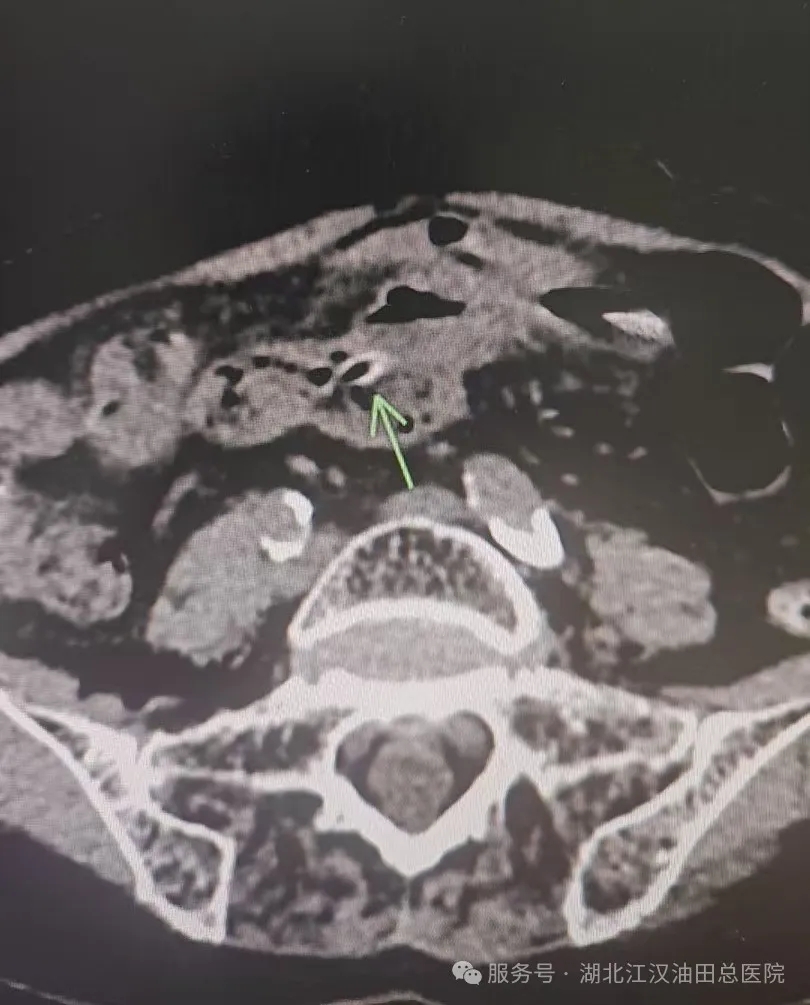

2月12号元宵夜,一位老年患者因右下腹痛急来我院就诊,经过我院普外科医生询问了解到患者近期食用过大枣,建议腹部CT检查,检查发现病因为异物刺破肠道引起穿孔伴腹膜炎,急诊手术也证实为枣核穿孔,术后恢复良好并顺利出院。这一案例为所有人敲响警钟:小小枣核,暗藏隐患,饮食安全切莫大意!